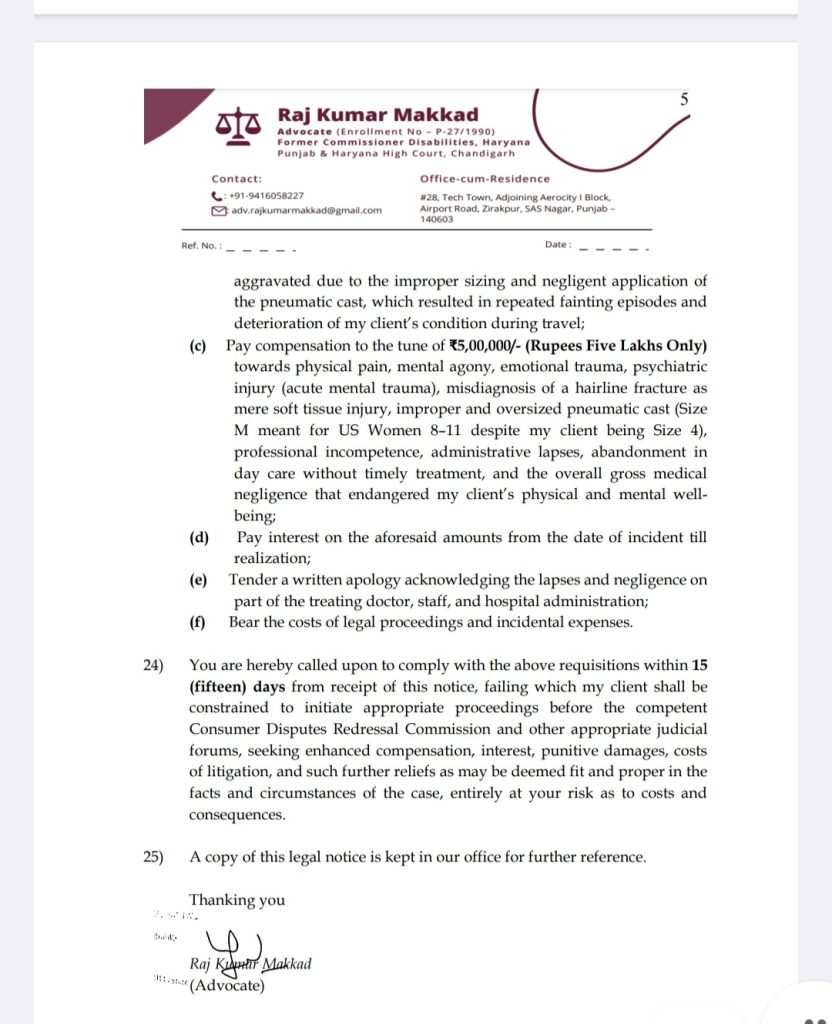

कानूनी नोटिस में कहा गया है कि अस्पताल की लापरवाही, गलत निदान, गलत साइज के कास्ट का उपयोग और समय पर उपचार न मिलने के कारण पीड़िता को शारीरिक पीड़ा के साथ-साथ गंभीर मानसिक आघात भी झेलना पड़ा।

नोटिस में उपचार पर हुए खर्च की वापसी, यात्रा व्यय की भरपाई और 5 लाख रुपये का मुआवजा देने की मांग की गई है। साथ ही अस्पताल से लिखित माफी की भी मांग की गई है। नोटिस में यह भी चेतावनी दी गई है कि यदि 15 दिनों के भीतर उचित कार्रवाई नहीं की जाती है तो मामले को उपभोक्ता आयोग और अन्य न्यायिक मंचों पर ले जाकर कानूनी कार्रवाई की जाएगी।